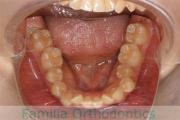

No.22V-449

- 主な症状:

- 上顎前突

- その他の症状:

- 叢生

- 年齢:

- 14歳

- 性別:

- 男性

- 抜歯部位

- 上:

- 44

- 下:

- 8448

- 主な使用装置:

- FEA

- 治療にかかった費用:

- 87万円

歯並びをきれいにしたいということで来院されました。上下左右から小臼歯を抜歯して、マルチブラケット法を行っています。2年弱、25回程度の通院が必要でした。

かなり強い叢生(でこぼこ、凹凸、ガタガタ)ですので、保定をしっかりしないと後戻りのリスクがあります。

- ≫治療前

-

上顎

下顎

前歯の関係など

右側

正面

左側

- ≫治療後